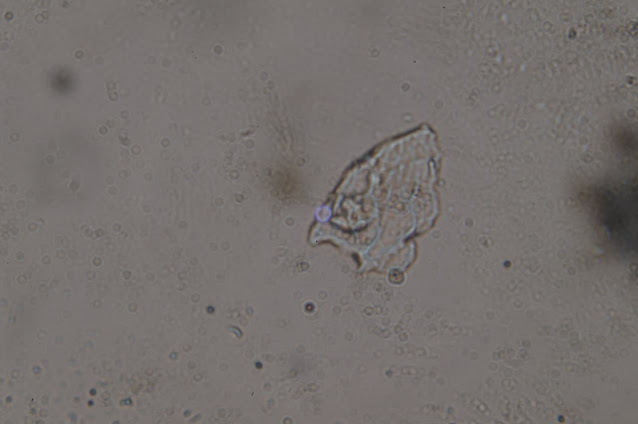

リカルド・デルガド:顕微鏡画像を見てみましょう。これは、ここスペインの別の医師(名前はまだ明かせませんが)が、バイアルの分析の一環として行った、Vaxigripインフルエンザワクチンに対する光学顕微鏡でのアプローチです。

これは本当に重要なことなので、お見せします。写真もありますが、後でビデオも作成します。最も重要な写真を選びました、いいですか?それを見せて皆さんの意見を聞きたいと思います。これはそのうちの1枚です。

ここにあるいくつかの結晶は、もしかしたらショ糖かもしれません。しかし、ここには折り目があります。別のものを見てみましょう。こちらの方が目を引きますね。

ご覧のように、この写真は倍率を下げて撮影しているので、遠くから観察したときの遠近感がよくわかります。しかし、これは、例えば、これらの組織は、酸化グラフェンと同じような特性を持っています。続けましょう。

これは、インフルエンザに対する、Vaxigripワクチンの小瓶からのものであることを思い出してください。インフルエンザワクチンの話です。ここでは、もう少し拡大してみました。光学顕微鏡のコンデンサーによって、明るさが異なります。

リカルド・デルガド これはかなりいい感じですね。ええ、折り目と端が自分自身に折り返されています。

リカルド・デルガド:かなりいい感じですね。そうですね。そして、これはいかなるワクチン中にもあるべきではないことを忘れてはいけません。

サンプルは左が昨年のあのVaxigripのインフルエンザワクチン、20209月・10月のものです。そして右は、別のコンデンサーで、科学文献に描かれているような酸化グラフェンを見ることができます。つまり、左のサンプルに見られるように、ひだがあり、いくつかの層が重なっています。右の写真と同じような特徴があり、ひだやエッジが折り重なっているのがわかります。非常によく似ています。このナノ材料を扱っている人や、光学顕微鏡や電子顕微鏡で見たことがある人に聞いてみると、「これも酸化グラフェンだ」と言われました。どうですか?これが20209月・10月のインフルエンザワクチン「Vaxigrip」です。